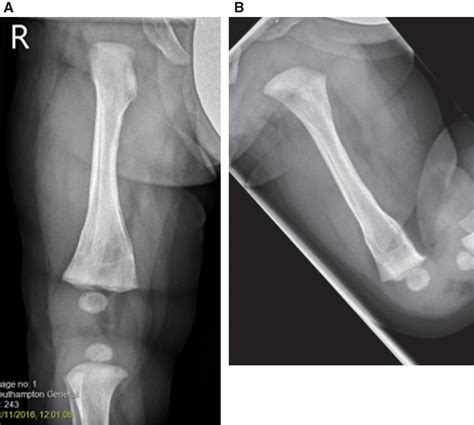

• X-rays: To rule out fractures or other bone issues.

• MRI (Magnetic Resonance Imaging): To provide detailed images of the soft tissues, including the meniscus, to confirm the diagnosis.